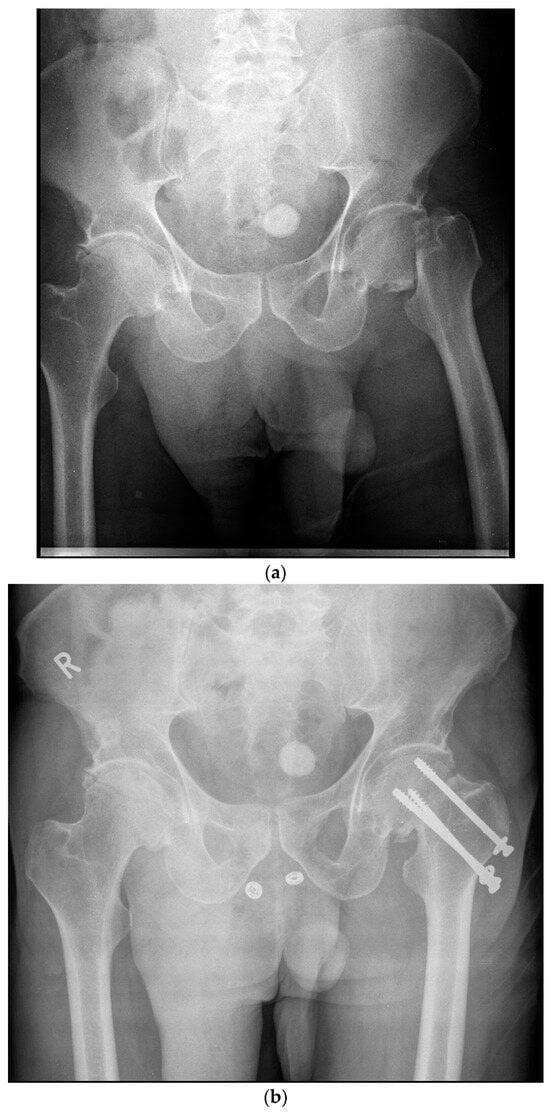

Figure 1.

(a)—Pre-operative X-ray demonstrating a left sided displaced femoral neck in a 59-year-old male. (b)—Postoperative X-ray demonstrating operative fixation of the same fracture with cancellous screws. R—Patient’s right side.